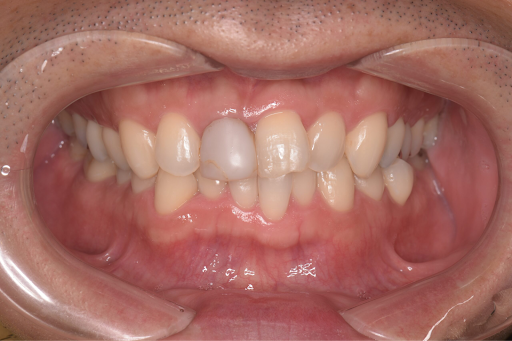

以下の症例写真例は、40代男性の症例です。

前歯のがたつきを改善するためにインビザラインによる矯正とセラミックインレー、根管治療を行い、金属を使わないメタルフリー治療を実施しました。

見た目と機能の両面で大きく改善している様子がわかります。

<Before>